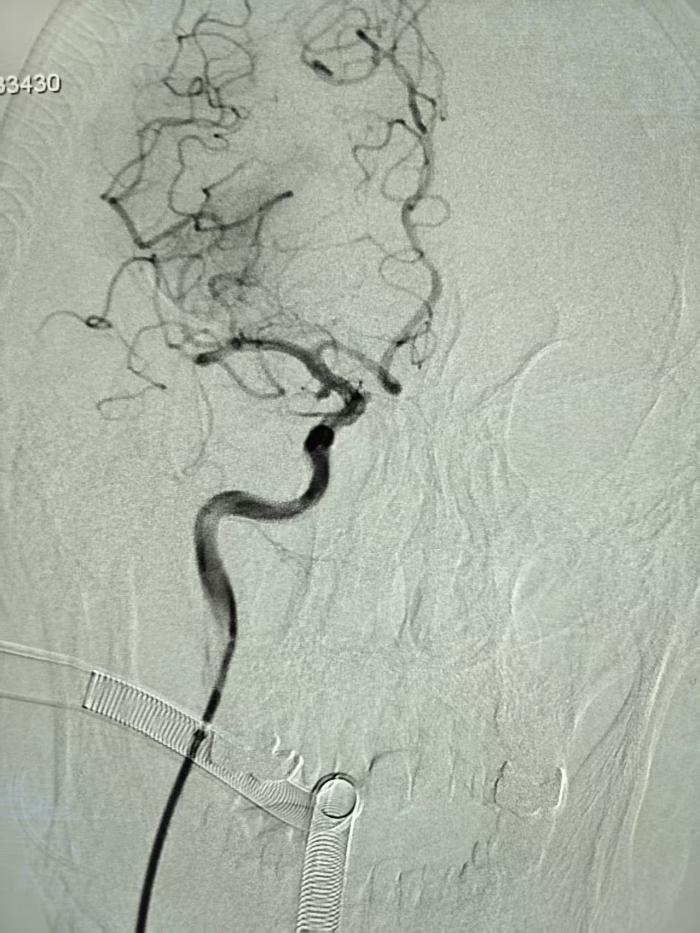

凌晨2时许,黄老先生突然瘫倒在家,左侧肢体完全瘫痪、意识模糊。120急救车抵达医院后,卒中绿色通道立即启动。头颅CTA检查揭示双重危机:右侧大脑中动脉M1段完全闭塞,同时右侧颈内动脉后交通段潜伏着一颗直径约4mm的动脉瘤。

“如同在布满裂缝的墙壁上拆除炸弹!”神经内二科副主任医师康敬源解释,III型主动脉弓本就增加导管到位难度,而动脉瘤在取栓操作中随时可能破裂出血,“要快速清除血栓,又要避免器械触碰动脉瘤,操作精度需控制在毫米级”。

步步惊心:三维路图引导下的“双线作战”

凌晨3:05,静脉溶栓药物注入患者体内,介入团队同步开展术前准备。面对血管严重迂曲,手术团队采用“长鞘+支撑导管+支架导管同轴技术”,利用三维血管路图精确定位。术中可见取栓支架释放后,血栓与动脉瘤相距不到2cm,主刀医生康敬源巧妙调整导管角度,以“悬空穿越”方式避开动脉瘤体,最终采取SWIM技术一次性取出多块混合型血栓,最大者4mm*2mm。